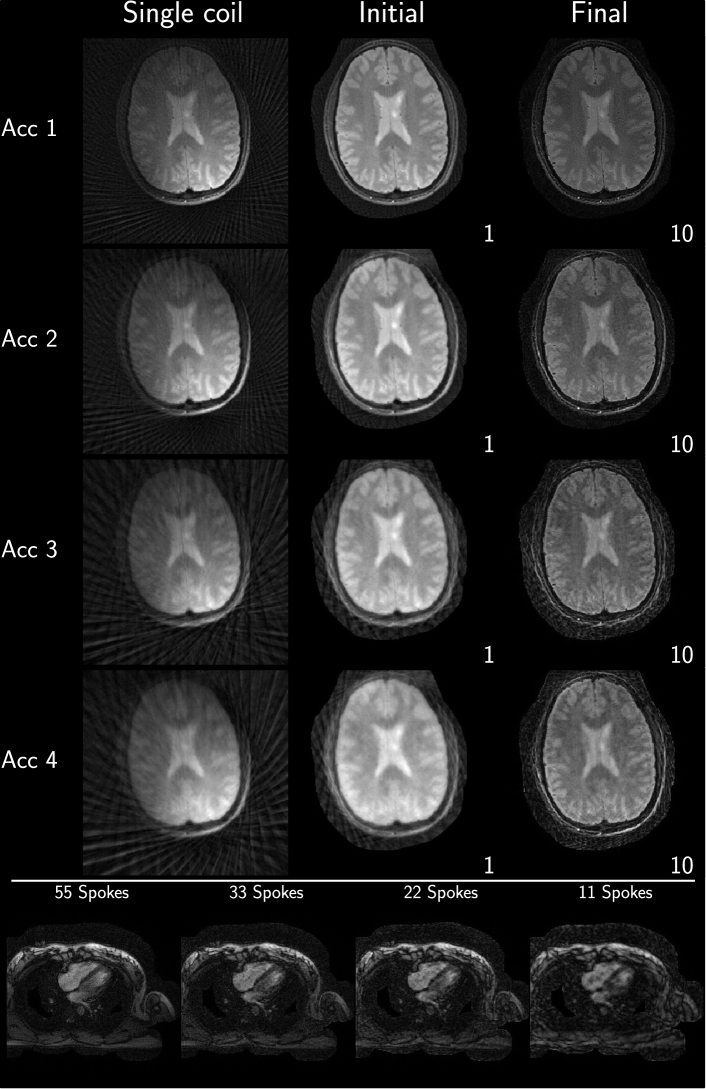

Example reconstruction results for an acceleration factor of 2, showing the image after evaluation of the right-hand-side of equation 3 (Initial) and after convergence of the algorithm (Final), from each submission are given in Figure 2 and Figure 3 for brain and heart data, respectively. All results are displayed with a window width from the minimum to the maximum occurring value in each image. Visually, intensity variations are noticeable owing to the different maximum values, however, contrast between different tissue seems to be similar in all submissions. Some submissions also use different FOVs for the brain (Eindhoven - no cropping, ETH - cropped to 340x340, Stanford - cropped asymmetrical to 300x300 ) compared to the others or different matrix sizes in the same FOV (USC - 256x256 and Utah - 512x512). No major structural differences are observable in the reconstruction except for the case of Eindhoven. The brain reconstruction from KI did neither use Tikhonov regularization nor early stopping, and the k-space was not filtered, resulting in a noisy appearance compared to other submissions. In addition, it shows a slight rotation to the left.

For the heart data, more differences are observed. Firstly, FOV differences occur more frequently (Eindhoven - cropped to 320x320, ETH - cropped to 360x360, NYU - cropped to 300x300, Stanford - asymmetric crop to 240x336). Secondly, matrix size in the same FOV and thus resolution is changed by some submissions (Berkeley - 300x300, USC - 256x256, Utah - 320x320). The heart reconstruction results for 11 spokes from Berkeley seem to be more noisy than the others. The reconstructions using the reference implementations, are given in Figure 4 and Figure 5 for Python and Matlab, respectively. Neither intensity nor contrast variations are visible between the two reference implementations.

Refer to caption

Figure 2: Example images after evaluation of the right-hand-side of equation 3 (Initial) and after termination of the algorithm for (Final) for each submission. Shown are results for acceleration factor of 2 of the supplied challenge brain data. All results are shown as they are returned by each algorithm. Visually observable differences include intensity variations among the reconstructions as well as some image center shifts and FOV differences. In addition, some reconstructions utilized image masks for the background.